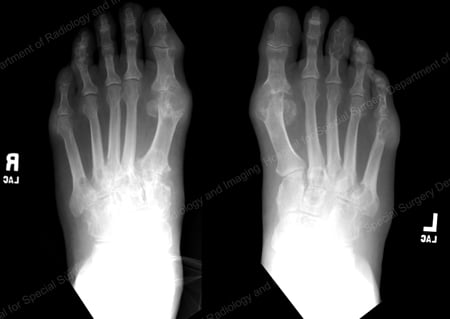

X-rays are the standard imaging technique for gout (See Figures 12-17: Figure 12: Gout of the Base of the 1st Toe; Figure 13: Gout of the Distal Finger Joints; Figure 14: Gouty Change and Soft Tissue Calcification About the Base of the 1st Toe; Figure 15: Gouty Destruction at Multiple Finger Joints; Figure 16: Gouty Erosion at the Proximal Ulna at the Elbow; Figure 17: Large Tophus Seen as Soft Tissue Mass at the Elbow) but in special cases, such as when gout needs to be separated from infection or tumor, magnetic resonance imaging (MRI) (Figure 18: MRI of the Knee Showing Gouty Soft Tissue Mass and Erosion of the Kneecap) or ultrasound (Figure 19: Power Doppler Study Showing Gouty Inflammation at the Base of the 1st Toe) will be helpful. A newer technique called a dual-energy CT scan (DECT) can show urate crystals in green color.

X-ray of gout at the base of the 1st toe

Figure 12: Gout of the Base of the 1st Toe

X-ray of gouty change and soft tissue calcification about the base of the 1st toe

Figure 14: Gouty Change and Soft Tissue Calcification about the Base of the 1st Toe